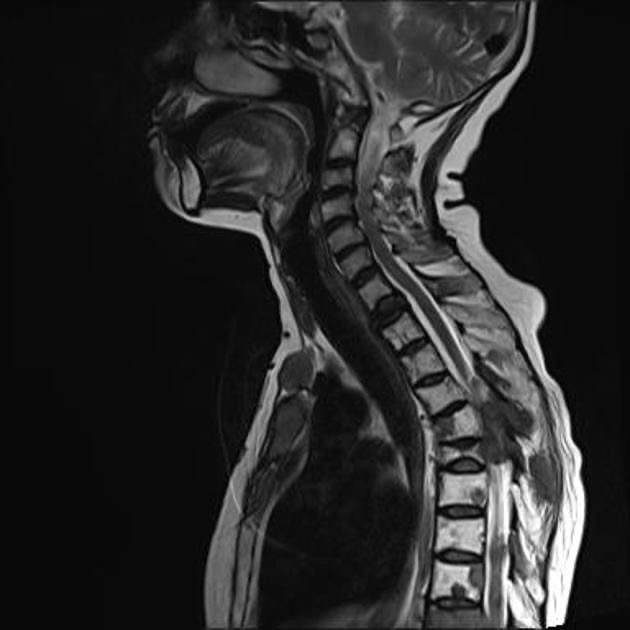

Чаще всего костные метастазы возникают в позвонках, на втором месте таз, далее следуют ребра и только после них – длинные трубчатые кости рук и бедренная кость.

• Сдавление спинного мозга возможно при переломах позвонков. При этом возникают тяжелые неврологические симптомы.

Широкие возможности предлагает хирургия. Кости можно укрепить пластинами, винтами, штифтами. При поражении позвонков применяют малоинвазивную методику – чрескожную пункционную вертебропластику. Во время этой процедуры в позвонок вводят иглу и заполняют его специальным полимерным составом – костным цементом. Он застывает внутри и придает прочность, помогает позвонку сохранять нужную высоту.